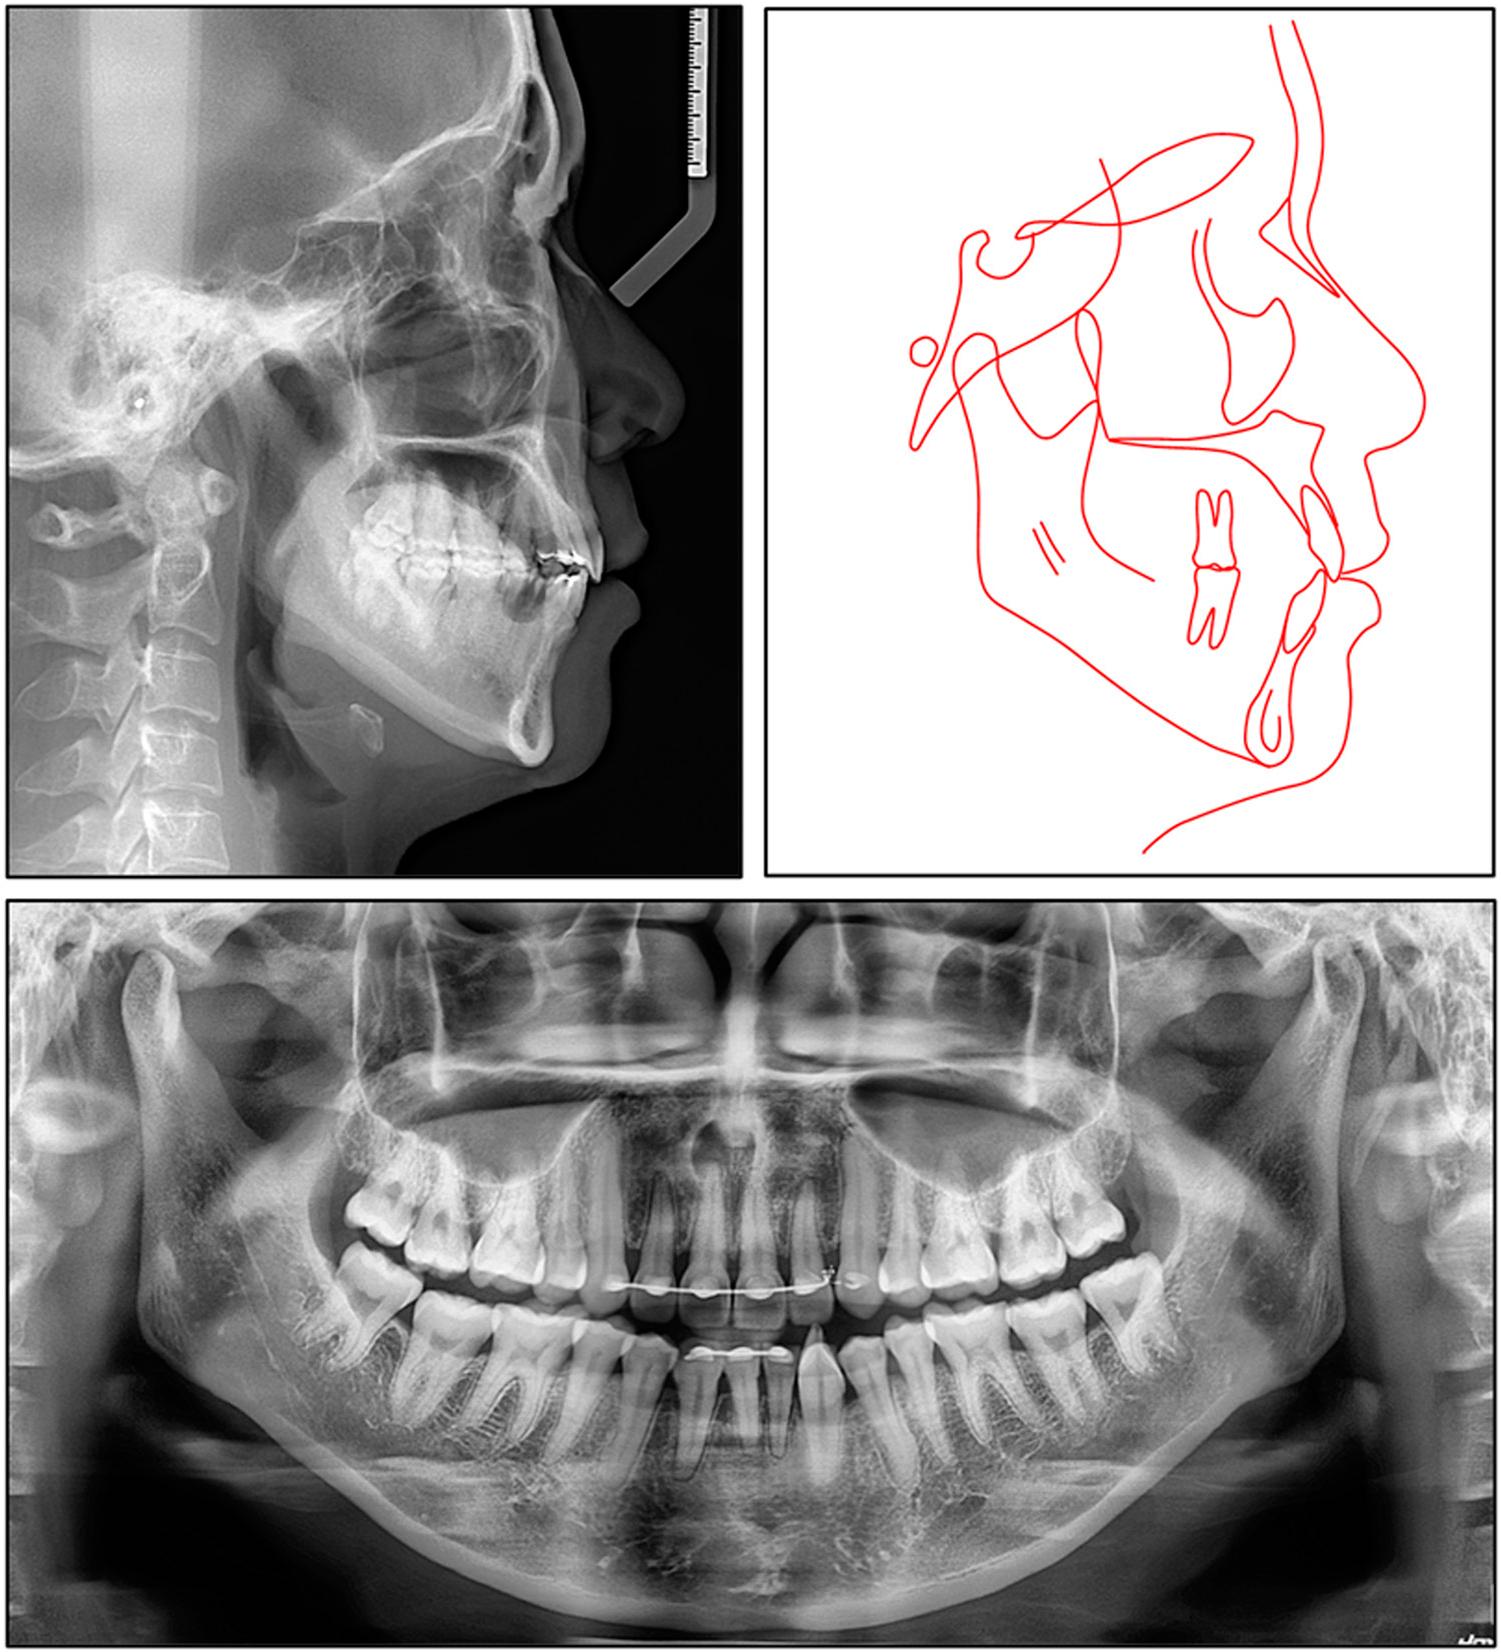

Figure 4.